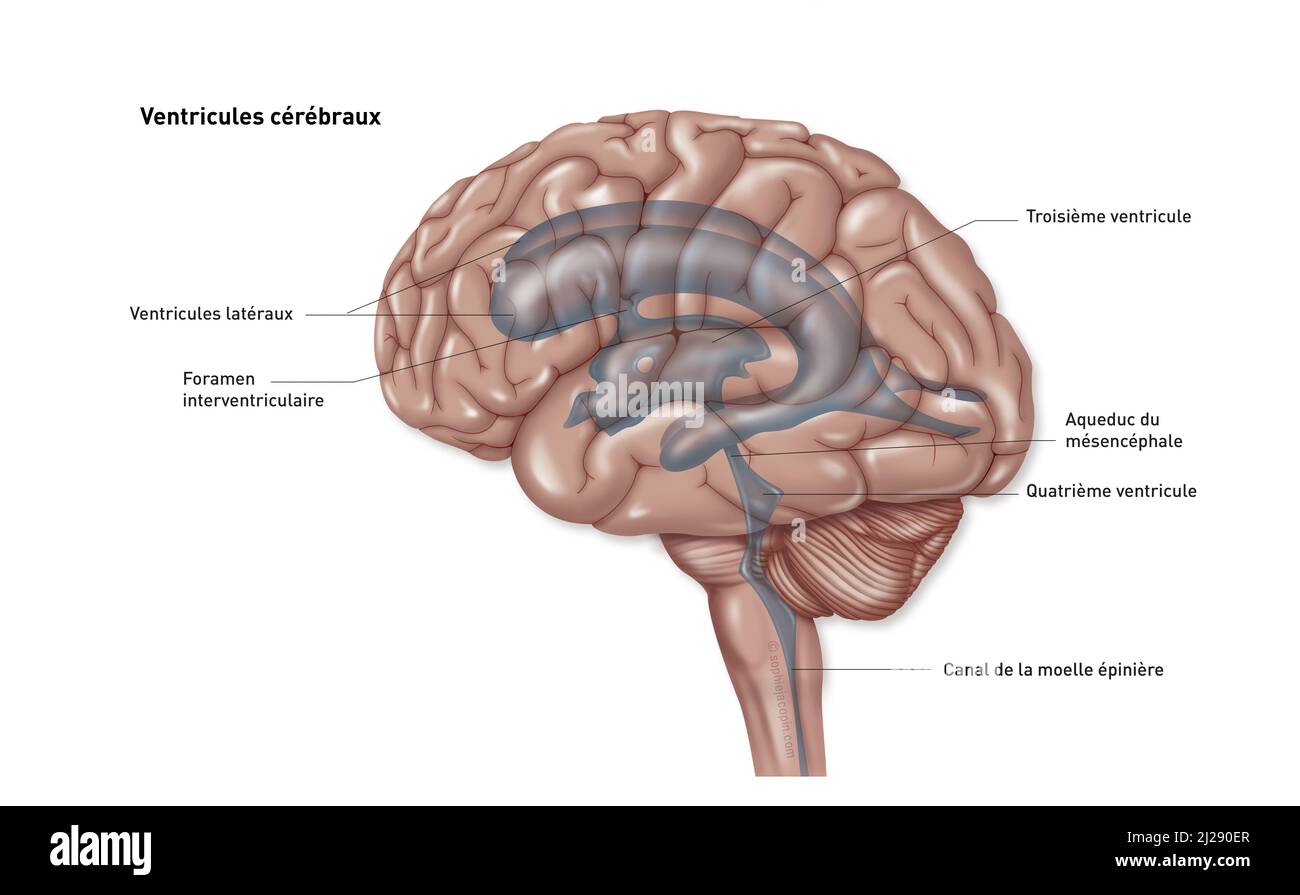

RF2T7NGWH–Ventrikel und zerebrales Aquädukt laterale Röntgenansicht 3D-Rendering-Illustration. Menschliches Gehirn und Ventrikelsystem Anatomie, Medizin, Gesundheitswesen, Scienc

RF2T7NGWK–Ventrikel und zerebraler Aquädukt lateral in Farben Röntgenbild-3D-Rendering-Illustration. Menschliches Gehirn und Ventrikelsystem Anatomie, medizinisch, gesund

RMBCE641–Sagittale Abschnitt des menschlichen Gehirns, Darstellung von Strukturen der zerebralen Ventrikel, Kleinhirn und Hirnstamm.

RF2T7NGWR–Ventrikel und Hirn-Aquädukt-Röntgenprofil Nahansicht 3D-Rendering-Illustration mit Körperkonturen. Anatomie des menschlichen Gehirns und des Ventrikelsystems,

RM2AWF8JC–Die Anatomie des Nervensystems, vom Standpunkt der Entwicklung und Funktion. -Ant. HornCentra, Teil Latcral vnnInf. Horn Q virale Pari Ant. Horn. Ventrikel Ventrikel Ventrikel Ventrikel Ventrikel Ventrikel Ventrikel Ventrikel Ventrikel Ventrikel Ventrikel Ventrikel Ventrikel Ventrikel Ventrikel Ventrikel Ventrikel Ventrikel Ventrikel Ventrikel ^^ 176.-Zwei Ansichten der Hirnventrikel des Menschen: A, Dorsale Ansicht; B, laterale Ansicht. Das Vorderhorn oder Cornu anterius ist der Teil, der rostral zum interventrikulären Foramen liegt. Seine Dach- und Rostrallgrenze wird von Thecorpus callosum gebildet. Sein mediales

RF2T7NGWW–Ventrikel und zerebraler Aquädukt in Farben Röntgenprofil Nahansicht 3D-Rendering-Illustration. Anatomie des menschlichen Gehirns und des Ventrikelsystems, medizinisch,

RF2T030GG–Röntgenlaterale Darstellung der Hirnventrikel 3D-Darstellung mit Körperkonturen. Anatomie des menschlichen und ventrikulären Systems, Medizin, Biologie, Scienc

RM2AWFNN9–Menschliche Anatomie, einschließlich Struktur und Entwicklung und praktische Überlegungen d in einem sagittalen mesialen Abschnitt (Abb. 910) wird jede dieser Teilungen als mit einem Teil des Systems der Kommunikation von Räumen verwandt angesehen, die als die dritten Ventrikel des Lateralands, der Aquädukt von Sylvius und der vierte Ventrikel die oben genannten Gehirnhemisphären ausdehnen. Durch den Hirnstamm und unter dem Kleinhirn bis zum zentralen Kanal des Rückenmarks. Da die lateralen Ventrikel zwei innumerieren, ist die Theirstellung im Zusammenhang mit den Gehirnhemisphären, in denen sie liegen, lateral zum m

RM2AN4TWY–Handbuch der allgemeinen, beschreibenden und pathologische Anatomie (Band 2). Ventrikel, ein. Ventrikel des Kleinhirns, b. Aquädukt von Sylvius, C. Dritten Ventrikel, d. Lateralen Ventrikel, 1. Vordere Horn, 2. Hintere Horn, 3. Absteigend Horn, II. Textur, III. Gewicht, IV. Konsistenz, Kap. Iii. Umhüllt des Gehirns. Abt. Ich. Pia - mater, I. des Rückenmarks, II. Von Hirn, ein. - Externe Pia mater, b. Interne pia-mater, ich. Choroid Plexus des vierten Ventrikel, ii. Choroid Plexus des Großhirns, Art.ii.Apert-syndrom Membran, Art. hi. Dura-mater, I. spinalen Dura-mater, II. Zerebrale Dura-mater